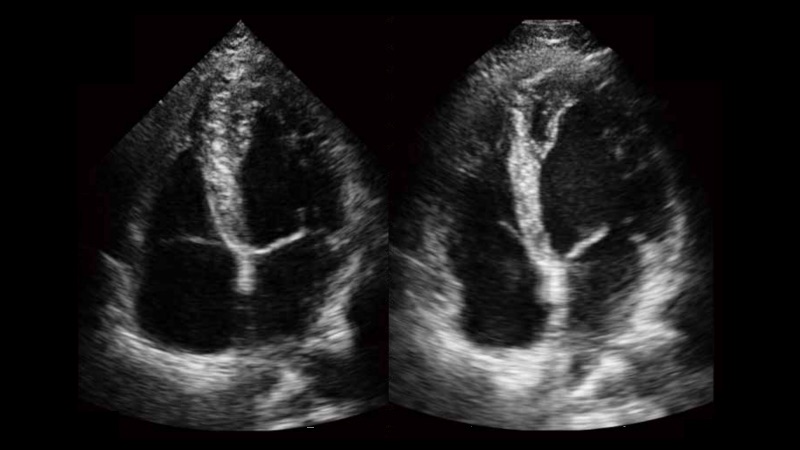

新一代微米成像技術大大提高了器官和病變的可見性。高清對比度分辨率將抑制斑點噪聲,同時保持真實的組織結構。